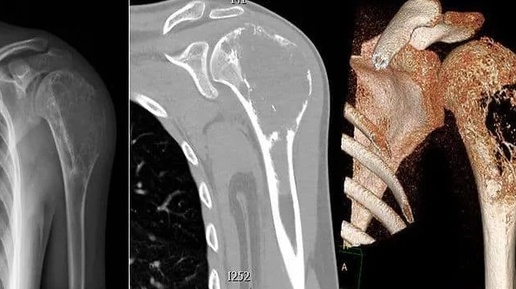

Опухоли костей — это аномальное разрастание клеток в костной ткани, которые может быть как доброкачественными, так и злокачественными. Они могут возникать в любой кости тела и влиять на ее структуру, что может вызывать болевые ощущения и другие осложнения. Понимание классификации, причин, симптомов и методов лечения опухолей костей важно для своевременной диагностики и эффективного лечения. Опухоли костей делятся на несколько категорий, в зависимости от различных факторов: Остеомы